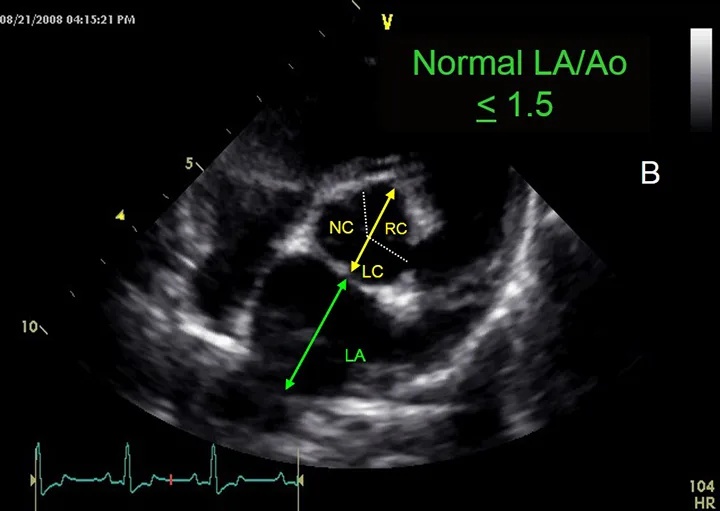

Figure 3B

Assessment of left atrial size. This image demonstrates the measurement of the aorta (yellow arrow) and left atrium (green arrow).

To assess the size of the left atrium, the transverse diameters of the aorta and left atrium are measured in the right sided short-axis view. Of note, other views can be used to obtain measurements, but these are the author’s preferred views. Measurements are taken in early ventricular diastole using the first frame after aortic ejection, where the Ao appears as a symmetric three-leaf clover with closed aortic valves and a teardrop-shaped LA.

1. To measure Ao, the first caliper is placed at the midpoint of the convex curvature of the wall of the right aortic sinus. The caliper cross is positioned as close as possible to the blood-tissue interface.

2. The second caliper is positioned at the point where the aortic wall and the noncoronary and left coronary aortic cusps merge. This measurement point is defined by a slight increase in echogenicity where the three structures merge.

3. The LA is measured from this point by extending the Ao line to the blood-tissue interface of the LA wall.

4. If a pulmonary vein enters the LA at the desired measurement point, the caliper is placed either on an extrapolation of the atrial border or immediately medial or lateral to the vein.2

• Image seen: In the view shown in this figure, the ratio of the left atrium (LA) to the aorta (Ao) should be <1.5:1 (also see Figure 3B).1